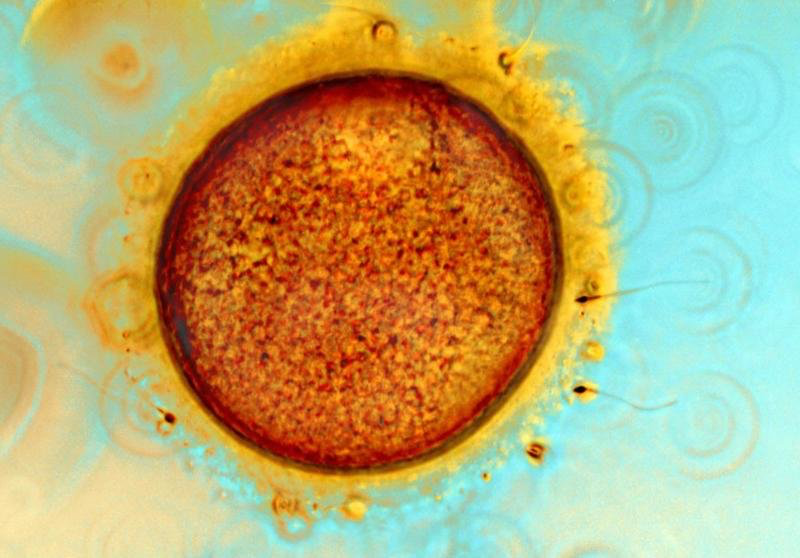

Human Ovum Fertilizing

Photo/ Light Micrograph, Spike Walker